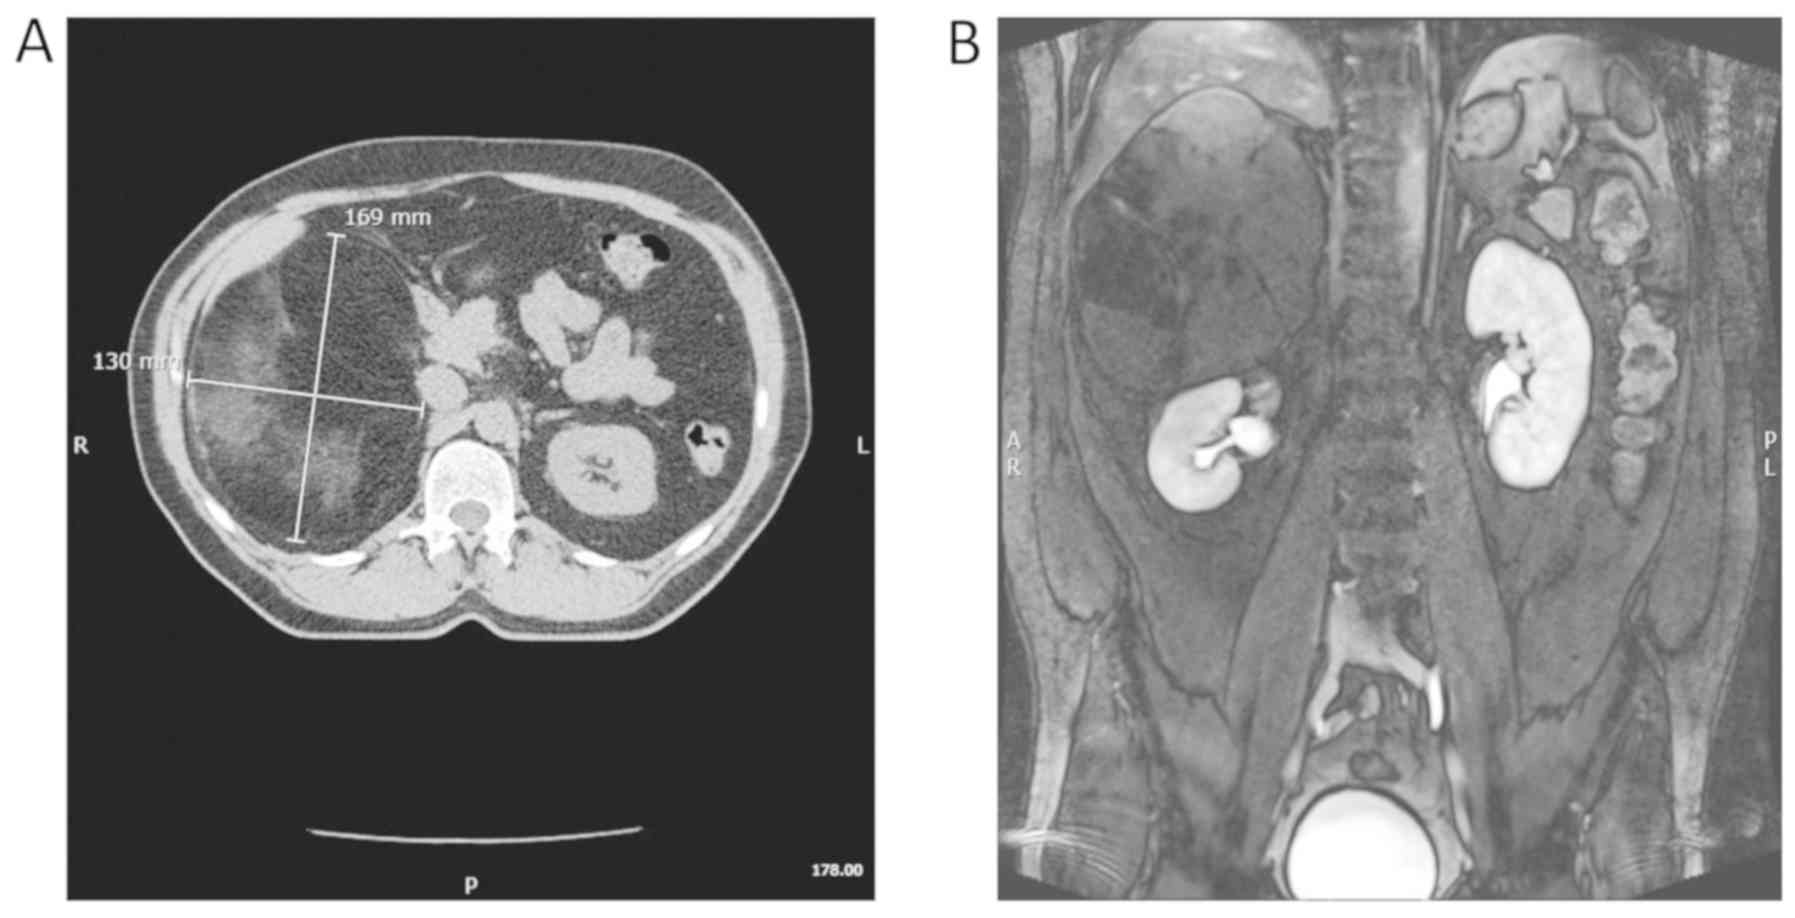

Adrenal myelolipoma is a rare mesenchymal tumour with benign biological behaviour that is mainly composed of mature adipose and myeloid tissue. Both sexes are equally affected, most commonly between the fifth and seventh decades of life. The diagnosis of adrenal myelolipoma is mostly incidental. Although it may occasionally be associated with necrosis, rupture and haemorrhage, causing abdominal pain, this tumour is usually asymptomatic. Consequently, management is conservative, while surgical treatment is reserved for symptomatic cases, or for masses growing quickly or to a size >6 cm. Giant myelolipomas (sized >10 cm) are rare. Open radical adrenalectomy is the standard treatment for giant myelolipomas, while the minimally invasive approach has been used in only few cases. We herein report the case of a patient with a giant adrenal myelolipoma who underwent robotic partial adrenalectomy. To the best of our knowledge, this is the largest giant adrenal myelolipoma treated with robotic surgery reported in the literature to date. A 55‑year‑old male patient underwent an abdominal computed tomography scan during follow‑up after radical prostatectomy for prostate cancer Gleason Score 6 (ISUP 1) due to biochemical recurrence. The examination revealed a right hypodense adrenal mass, sized 16x13 cm. Abdominal magnetic resonance imaging confirmed the presence of characteristics suggestive of a myelolipoma. The patient did not report any symptoms. Due to the benign characteristics of the mass, robotic partial adrenalectomy and enucleation of the mass were performed. The operative time and estimated blood loss were 205 min and 100 ml, respectively. No intra‑ or postoperative complications occurred. The patient was mobilized on the first postoperative day and the time to flatus was 36 h; the length of hospitalization was 4 days. Histological examination confirmed the diagnosis of adrenal myelolipoma, sized 18x11.5x6 cm. No tumour recurrence occurred over a follow‑up period of 12 months. In conclusion, robotic surgery allows performing partial adrenalectomy with a lower risk of bleeding and with preservation of healthy adrenal tissue, which is of paramount importance for the patient as it reduces recovery time and the need for medical substitution therapy.

Figure 1

Figure 2

Figure 3